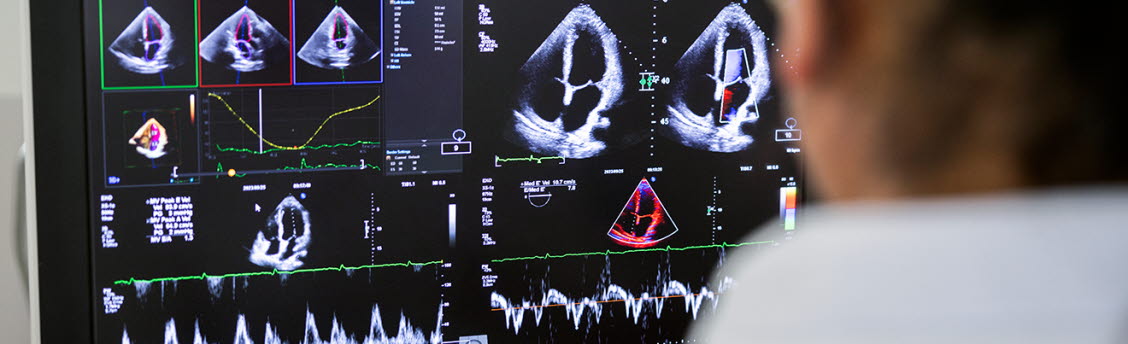

Rytmrubbning

Studier visar att varje ytterligare standardglas alkohol en person dricker per dag resulterar i 8 % ökad risk för att drabbas av förmaksflimmer. Man ser också olika samband beroende på alkoholtyp, störst riskökning ger starksprit. Oavsett veckokonsumtionens storlek är även berusningsdrickande en oberoende riskfaktor. Man kan också notera att risken för förmaksflimmer ökar vid sömnbrist, stress och kaliumbrist. Dessa är alla tillstånd som kan orsakas av alkohol.